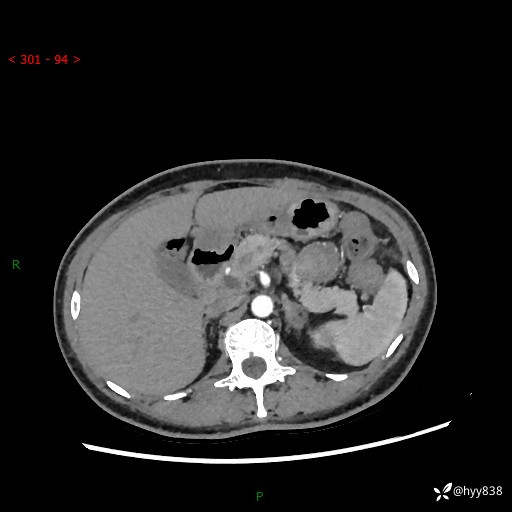

胰腺CT平扫

img